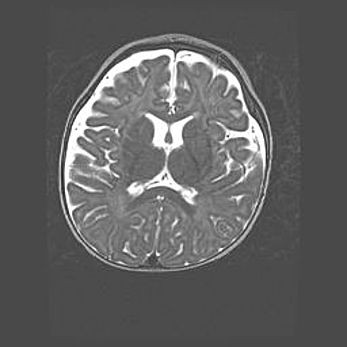

Открытая гидроцефалия.

Возраст: 9 месяцев 12 дней

Вес: 6800 г

Пол: мужской

Окружность головы: 41,5 см

Срок гестации: 28 недель

Гидроцефалия головного мозга у новорожденных имеет характерный признак: опережающий рост окружности головы приводит к визуально хорошо определяемой гидроцефальной форме сильно увеличенного в объёме черепа. Детские неврологи определяют следующие симптомы гидроцефалии у грудничков: выбухающий напряжённый родничок, частое запрокидывание головы, смещение глазных яблок к низу.